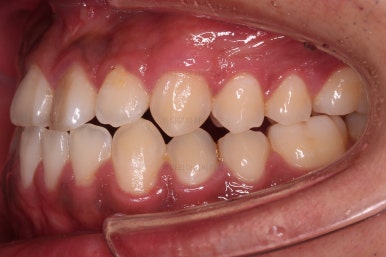

초진 시 입안의 모습입니다.

비교적 고른 편이긴 하나 아랫니가 전반적으로 밀려 나오면서 앞니끼리 부딪혀 있는 양상이고요.

어금니 맞물림도 긴밀하게 톱니바퀴처럼 위아래가 맞물려 있는게 아니라 엉성한 모습이죠.

앵글씨 3급 부정교합이라고 하는데요.